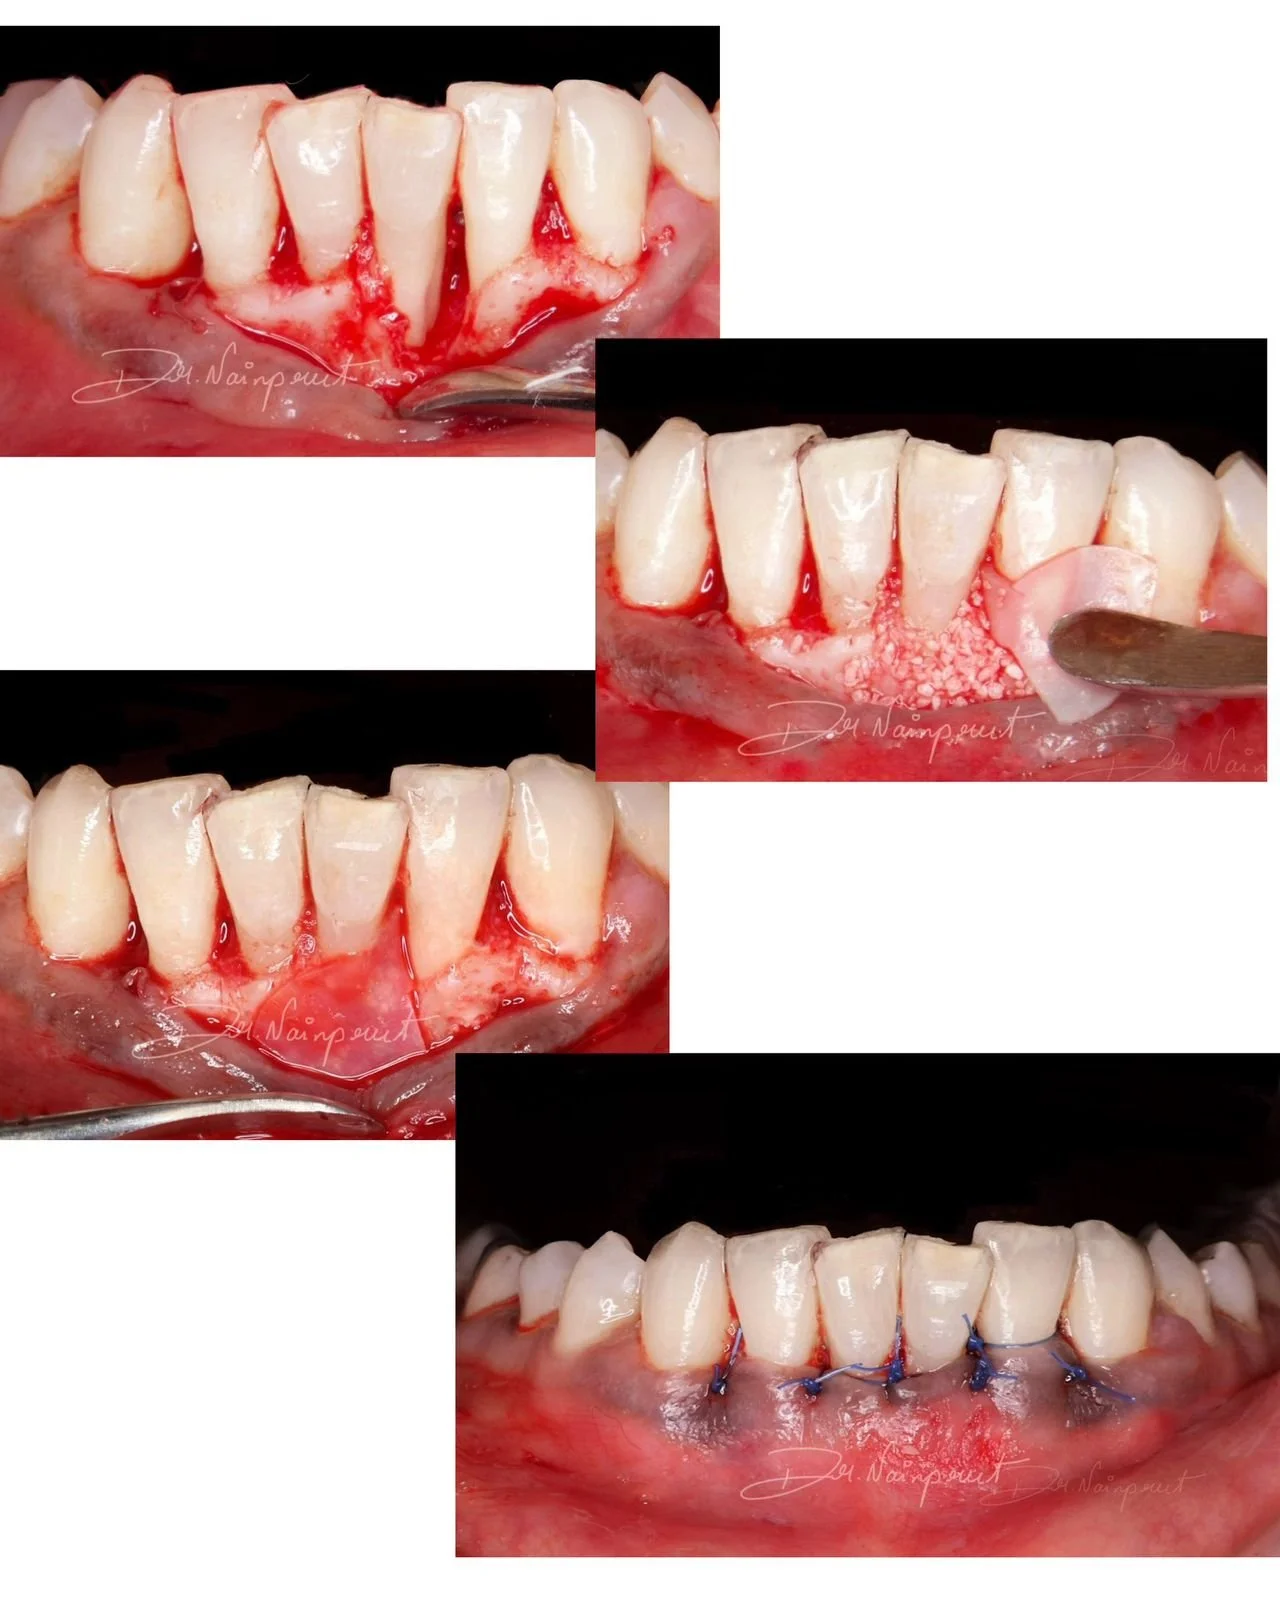

PAPILLA RECONSTRUCTION SURGERY WITH CONNECTIVE TISSUE GRAFT (Lower anteriors)

Surgery performed by Dr Mohammed Thaha